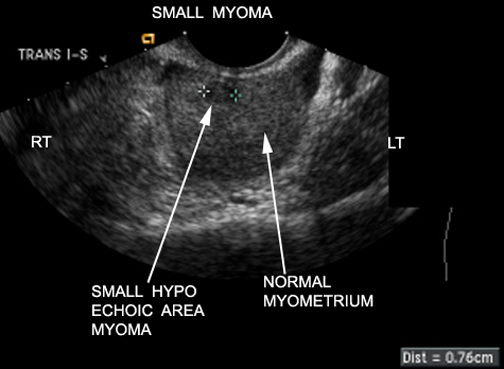

Doctors typically diagnose fibroids using:

Pelvic examination

Ultrasound scan

MRI scan (for detailed assessment)